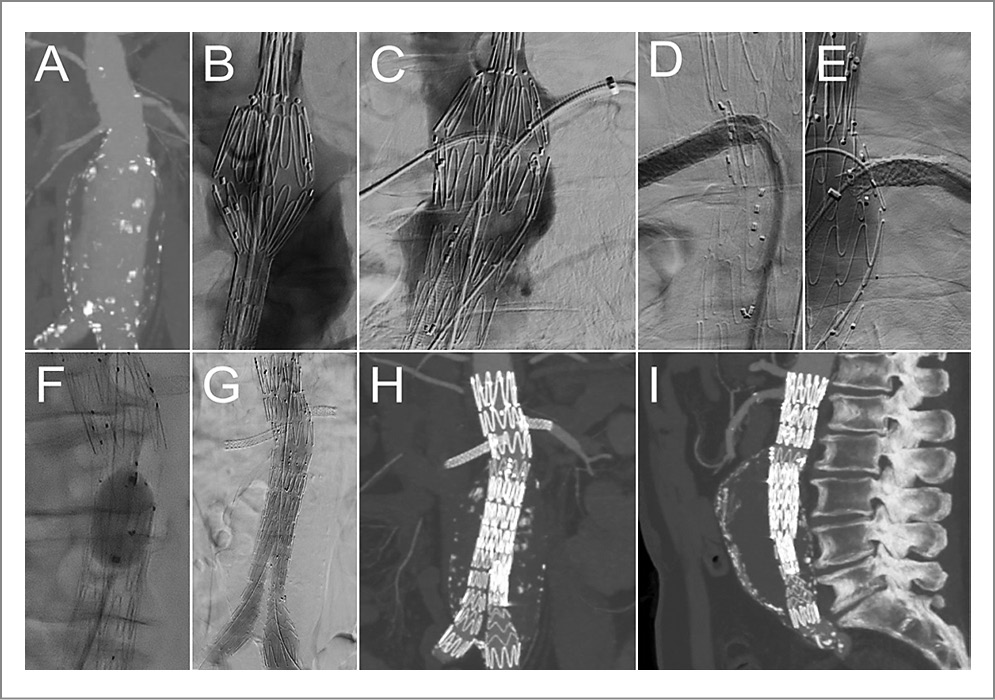

С целью улучшения позиции для имплантации и сопоставления ФСГ с ПА применялось программное обеспечение 3D Fusion. Так, I этапом по сверхжесткому проводнику Lunderquist® (Сook Medical, США) в брюшной отдел аорты заведен фенестрированный компонент. Выполнено его частичное раскрытие без открытия проксимальной короны. Затем последовательно катетеризированы правая и левая ПА, в которые установлены интродьюсеры 7 Fr. Выполнено полное открытие ФСГ. В правую и левую ПА последовательно имплантированы стенты-графты Bentley (InnoMed, Германия) 6,0×28 мм и 7,0×27 мм соответственно. Позиционирование и имплантация бифуркационного компонента с перекрытием дистального края раннее установленного стент-графта выполнены II этапом. Далее имплантирована бранша в левую общую подвздошную артерию. Выполнена постдилатация зон перекрытия и компонентов графтов баллонным катетером Reliant (Medtronic Inc., США). При контрольной интраоперационной аортографии выявлено выключение АБА из магистрального кровотока с сохранением кровотока по всем висцеральным артериям. Гемостаз мест доступов выполнен с помощью систем для ушивания мест доступов ProGlide (Abbott Vascular Inc., США). Ход оперативного вмешательства представлен на рис. 1.

Рис. 1. Клинический пример 1. ЭВП заранее подготовленным ФЭГ: А – МСКТ-АГ брюшной аорты, прямая проекция; В – начальный этап имплантации: открыто 1-е звено и частично раскрыто 2-е, совмещены метки ЭВПр с устьями артерий; С – имплантация ЭГ, катетеризированы устья ПА, через интродьюсеры 7 Fr заведены стент-графты в ПА; D, E, F, G – последовательная имплантация стент-графтов в ПА; H – контрольная аортография: позиция ЭГ удовлетворительная, аневризма выключена из кровотока; I, J – контрольная МСКТ-АГ в госпитальный период: отмечается полное выключение аневризмы из кровотока.

Время рентгеноскопии составило 53 мин, объем контрастного вещества – 210 мл. По данным контрольной госпитальной МСКТ-АГ аневризма выключена из кровотока, подтеканий не выявлено. На 3-и сутки после вмешательства пациент в удовлетворительном состоянии выписан под наблюдение по месту жительства.